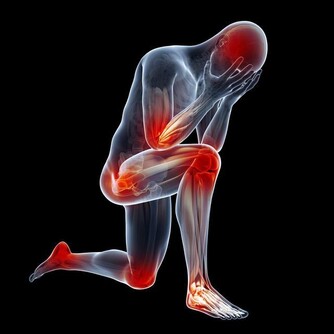

與著涼、飲食不潔等導致的急性腹瀉不一樣,慢性腹瀉原因比較複雜。

首先,從腸道本身來看,如果持續腹瀉,還伴隨發燒、血便、體重減輕,有可能是炎症性腸病,如潰瘍性結腸炎、克羅恩病;這是兩種疾病,但都因為頻繁腹瀉,吸收差,會導致人非常虛弱。

其次,一些全身性疾病,如結核、甲亢等也會造成慢性腹瀉。

這些都是需要及時發現、治療的疾病,否則不管是疾病本身,還是腹瀉帶來的消耗,都對人的健康帶來巨大的威脅。